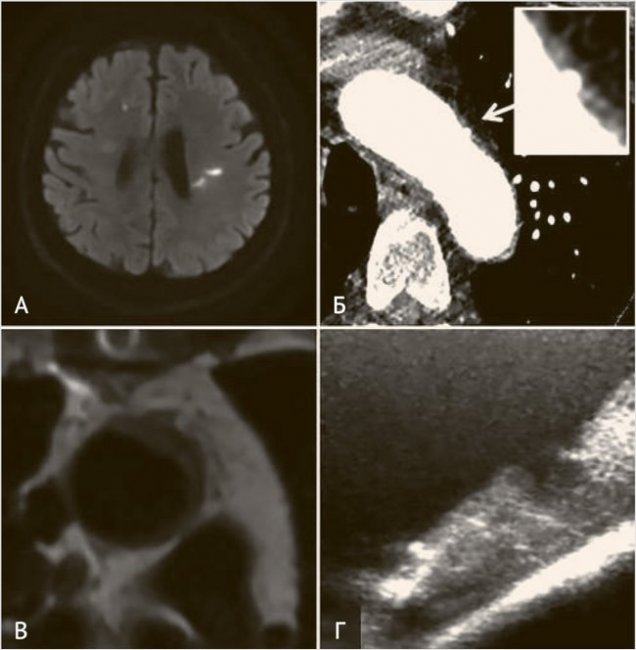

Традиционно золотым стандартом выявления АДА является ЧП-ЭхоКГ, однако к существенным недостаткам исследования относятся участок слепой зоны от воздуха в трахее, полуинвазивность метода и частая необходимость седации [24]. Мы считаем КТ-ангиографию (КТА) оптимальным методом диагностики атером аорты, так как это исследование позволяет верифицировать значимый супракардиальный атеросклероз на экстраи интракраниальном уровнях (из недостатков – артефакты пульсации в восходящей аорте при отсутствии ЭКГсинхронизации). Реже для выявления АДА выполняется МРТ-исследование аорты. В случае кардиохирургических операций возможно применение эпиаортального УЗИ [25] (рис. 1).

Рисунок 1. Атероматоз аорты

Пример паттерна острых инфарктов на DWI МРТ (А) у пациента с атеромой дуги аорты, выявленной при проведении КТ-аортографии (Б). Пример атеромы дуги аорты на МРТ аорты с ЭКГ-синхронизацией (В) и интраоперационном эпиаортальном УЗИ (Г) при выполнении кардиохирургической операции.

К МР-особенностям инсультов на фоне осложненных АДА относятся мультитерриториальные инфаркты, частота которых в исследовании NAVIGATE-ESUS составила 21% (у пациентов без АДА – 13%). В случае одиночных инфарктов чаще вовлекается левый каротидный бассейн (54% против 32% в правой гемисфере), что связано с частым расположением атером дистальнее брахиоцефального ствола [26].